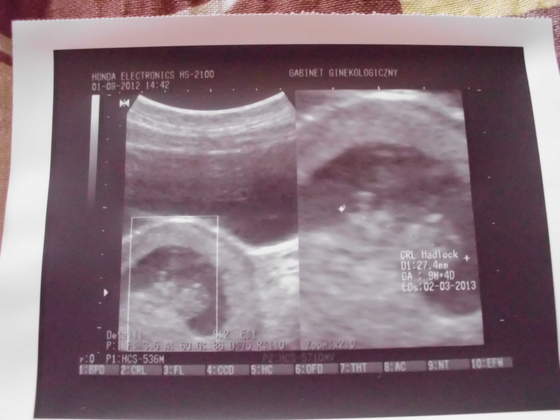

IMG_0453.jpg IMG_0454.jpgIMG_0455.jpgIMG_0456.jpg przedstawiam wszystkim cioteczką z bb moje małe szczęście:)